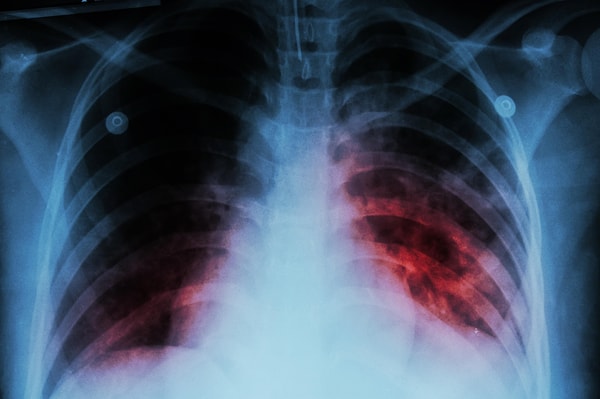

Tarihte kurbanlarını aşırı solgun bıraktığı için bu isimle anılan tüberküloz, akciğerleri hedef alarak vücudu adeta içten içe tüketiyor. Dr. Robert Redfield gibi önemli isimler, tüberkülozun doğru tedavi edilmediği senaryolarda koronavirüsten çok daha yüksek bir öldürme oranına sahip olduğuna dikkat çekiyor. Modern varyantların tedaviye yanıt vermemesi, sağlık otoritelerini küresel bir kriz ihtimaline karşı harekete geçirmiş durumda.

Halk sağlığını korumak adına yetkililer, belirtiler konusunda her zamankinden daha dikkatli olunması gerektiğini hatırlatıyor. İki haftayı geçen inatçı öksürük, göğüs bölgesinde hissedilen ağrılar, kan tükürme, gece terlemeleri ve bitmek bilmeyen yorgunluk tüberkülozun en net habercileri arasında yer alıyor. Erken teşhisin hem bireysel kurtuluş hem de toplumsal yayılımın durdurulması için tek çare olduğu belirtilirken, hükümetlerin riskli bölgelerde geniş çaplı tarama hazırlığı içinde olduğu bildiriliyor.